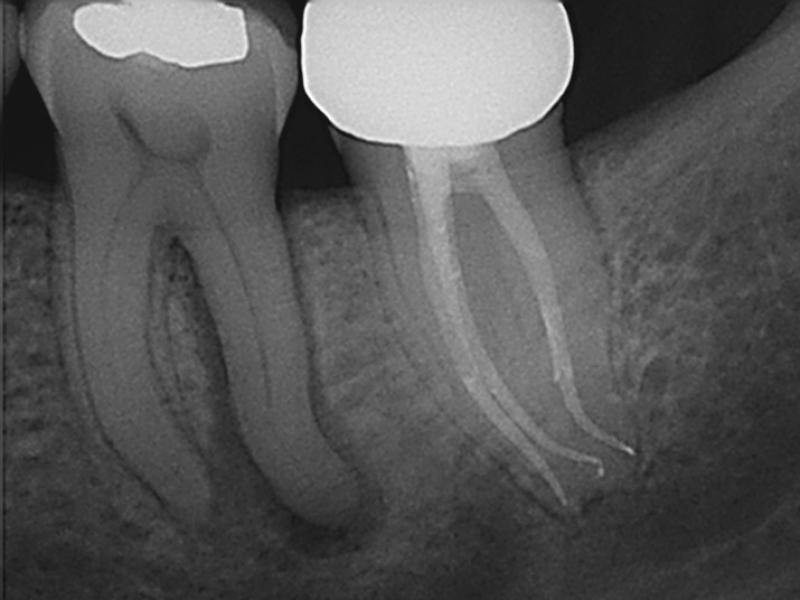

Post-Op